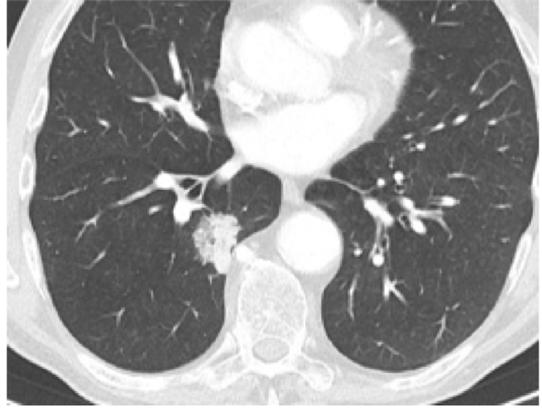

Mynd 6-1 Lítið lungnakrabbamein í hægra lunga (ör) sem fannst við skimun með tölvusneiðmyndum.

Með tilkomu tölvusneiðmyndatækni (TS) varð unnt að finna mun smærri hnúta í lungum en áður var mögulegt með hefðbundnum röntgenmyndum (mynd 6-1). Á síðustu áratugum hefur verið efnt til stórra framvirkra samstarfsverkefna, bæði í Bandaríkjunum og Evrópu. Fyrstu rannsóknir á skimun með TS voru gerðar í Japan og fyrsta alþjóðlega rannsóknin benti til þess að unnt væri að finna um